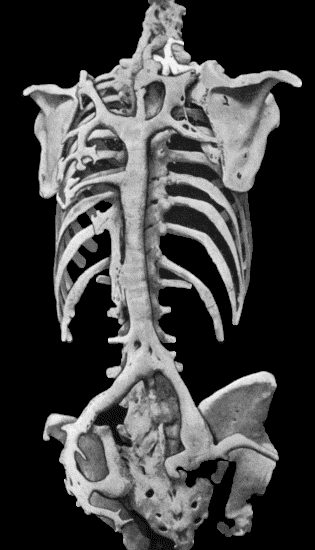

133.Skeleton of Rickety Dwarf 470

134.Changes in the Skull resulting from Ostitis Deformans 474